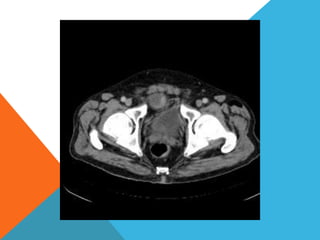

El paciente presentó síntomas de sangrado digestivo y pérdida de peso. Exámenes revelaron gastritis crónica asociada a H. pylori. Un tumor fue descubierto en una colonoscopia normal. La cirugía removió un tumor fibroide solitario, una rara neoplasia mesenquimal que usualmente crece lento y tiene bajo potencial de malignidad. El pronóstico después de la remoción quirúrgica es generalmente bueno.